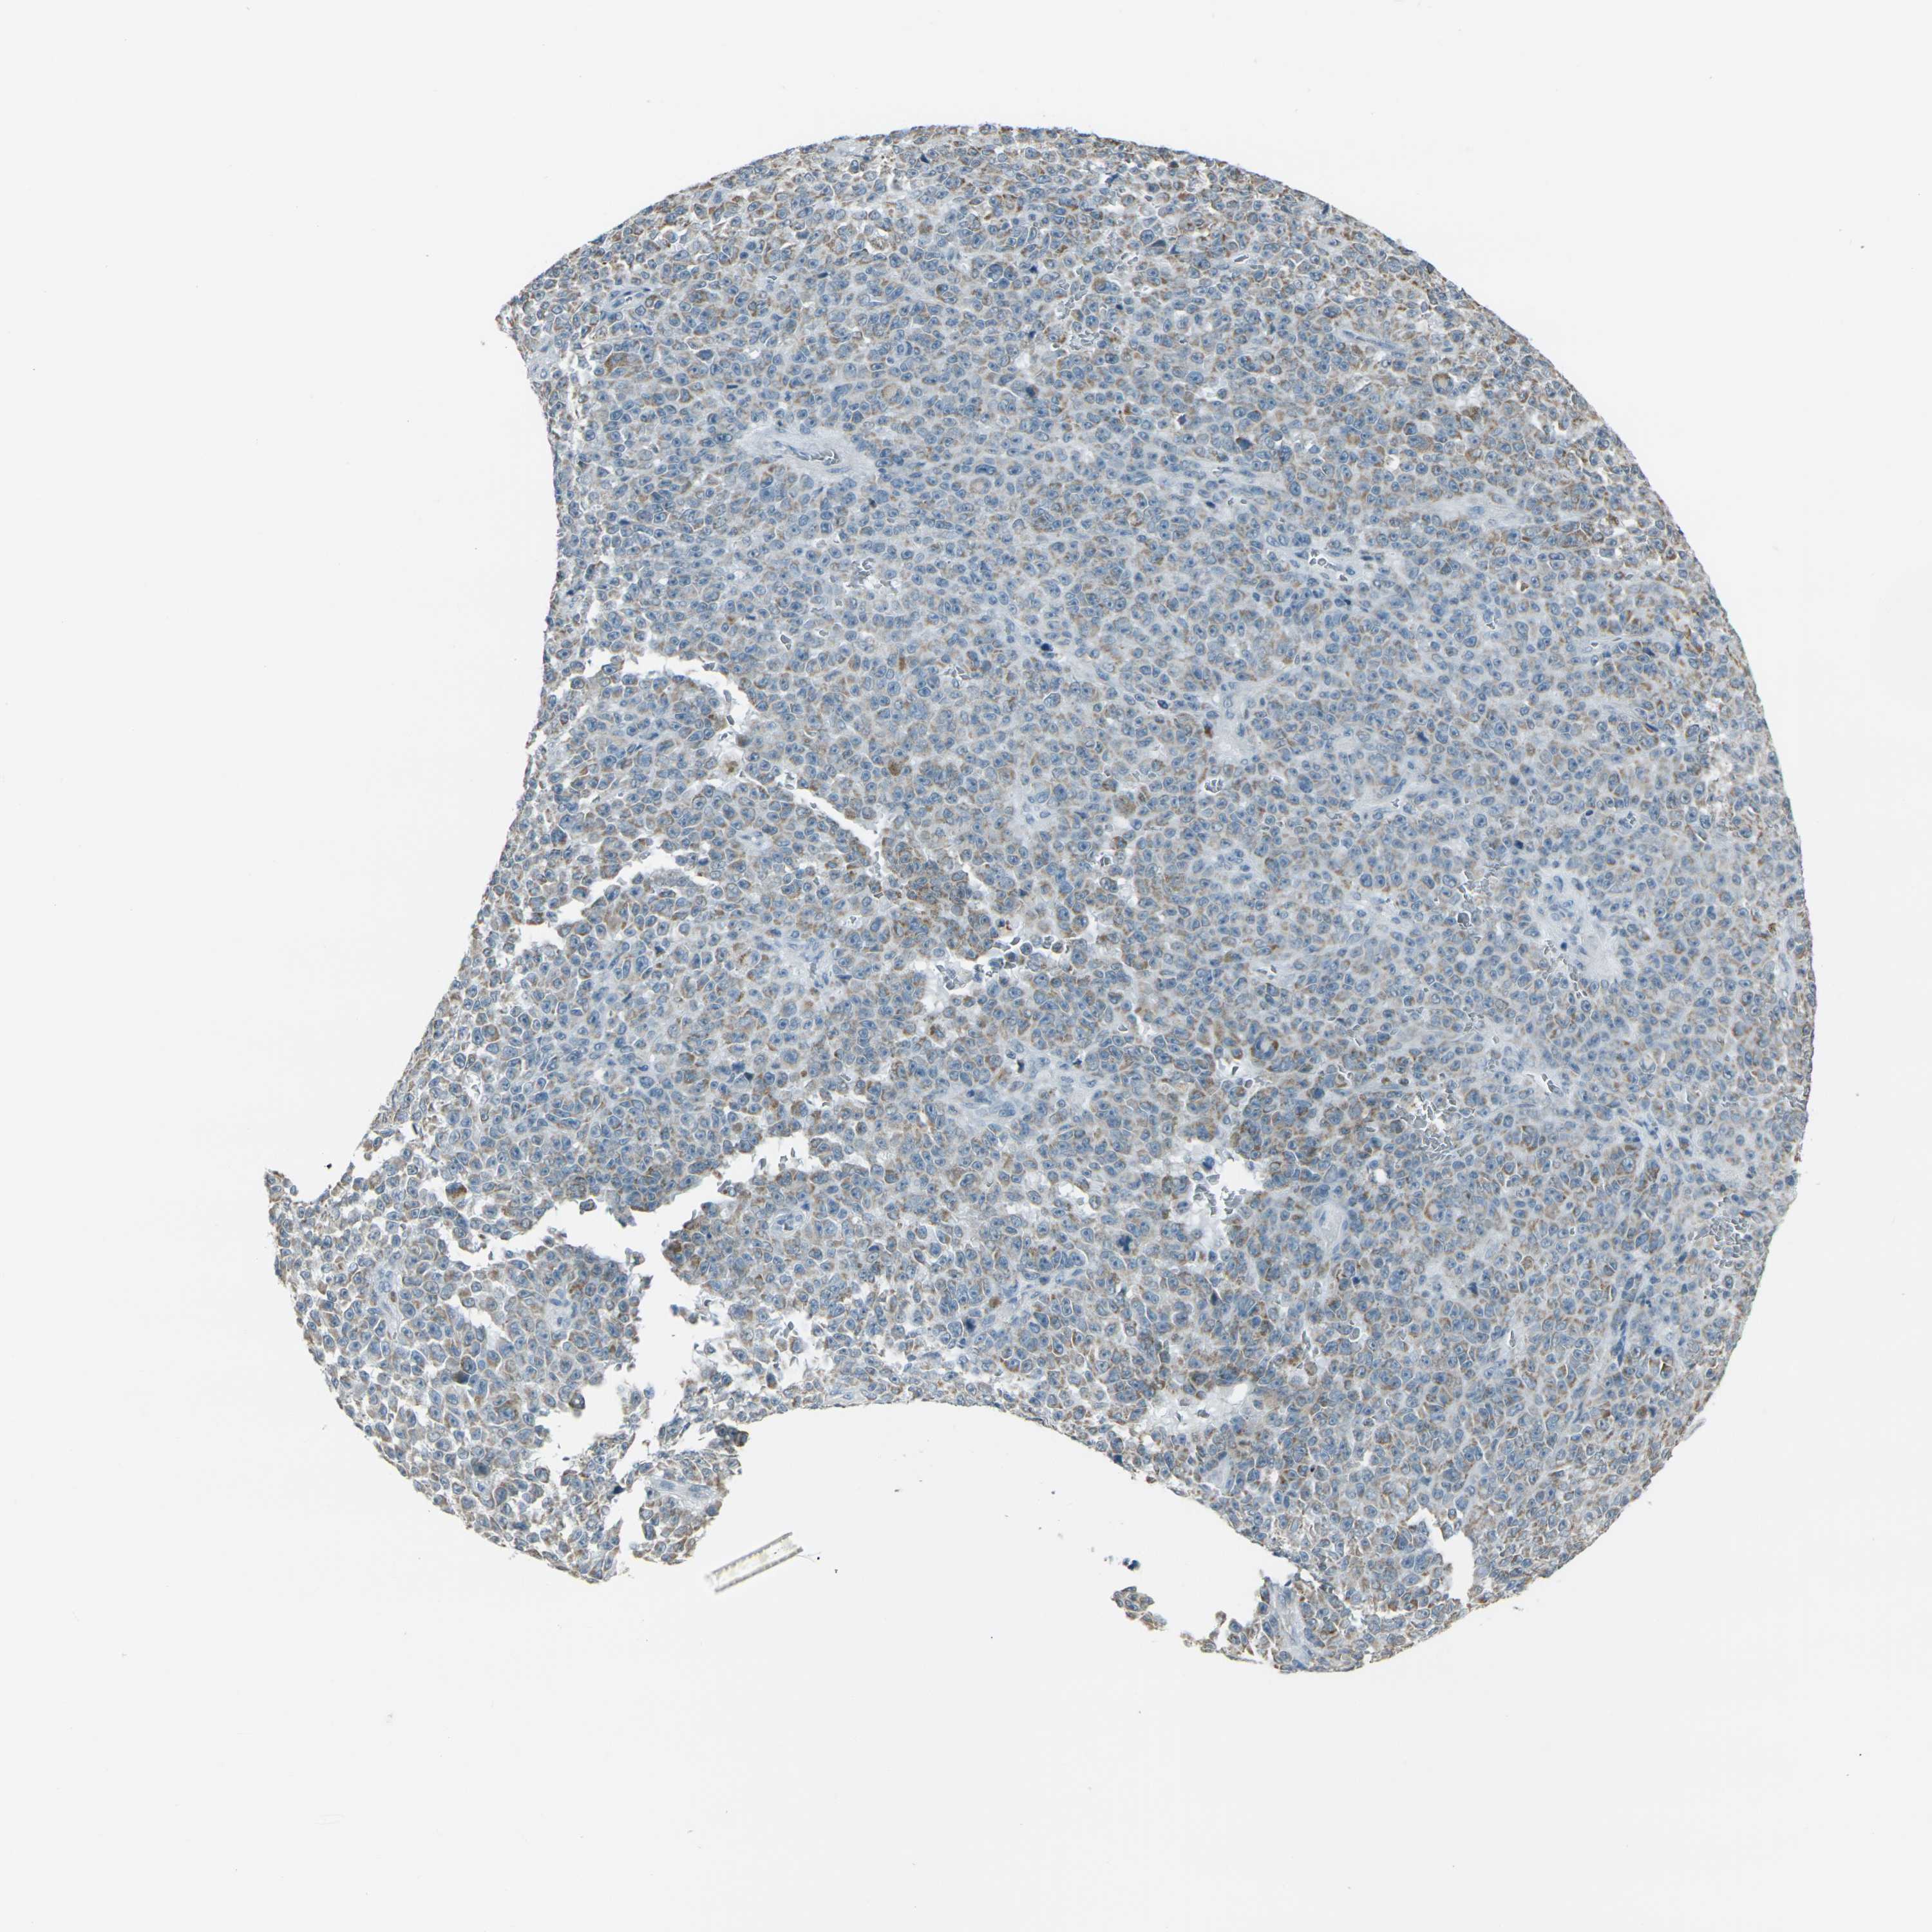

MELANOMA - Protein expressioni

A mouse-over function shows sample information and annotation data. Click on an image to view it in a full screen mode. Samples can be filtered based on level of antibody staining by selecting one or several of the following categories: high, medium, low and not detected. The assay and annotation is described here.

Note that samples used for immunohistochemistry by the Human Protein Atlas do not correspond to samples in the TCGA dataset.

Antibody stainingi

Antibody staining in the annotated cell types in the current human tissue is reported as not detected, low, medium, or high, based on conventional immunohistochemistry profiling in selected tissues. This score is based on the combination of the staining intensity and fraction of stained cells.

Each image is clickable and will lead to virtual microscopy that enables deeper exploration of all samples and also displays staining intensity scores, fraction scores and subcellular localization as well as patient and tissue information for each sample.

Antibody HPA042205

Antibody HPA043013

Antibody CAB011603

Staining

High

Medium

Low

Not detected

Intensity

Strong

Moderate

Weak

Negative

Quantity

>75%

75%-25%

<25%

None

Location

Nuclear

Cytoplasmic/membranous

Cytoplasmic/membranous,nuclear

Malignant melanoma, NOS

Malignant melanoma, Metastatic site

Malignant melanoma in situ